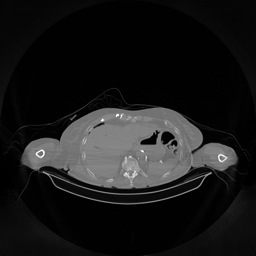

The results for simulated noisy data are shown in Fig. 2. The first and third rows display two representative slices from the test set, and the second and fourth rows present the corresponding error maps. The traditional WCE method suppresses cupping artifacts and recovers some missing anatomical structures but still shows noticeable deviations from the ground truth. Predictions from the four diffusion-based models demonstrate a markedly improved ability to restore anatomical structures. Among them, cDDPM fails to fully reconstruct the patient bed and retains residual noise in its outputs. This noise is attributable to an incomplete reverse denoising process rather than residual Poisson noise, as evidenced in our noise-free experiments (Fig. 5 in the Appendix). PatchDiffusion, diffusionGAN, and I2SB achieve similar visual quality, with I2SB producing the cleanest and most consistent reconstructions.

Quantitative results in Tab. V further confirm I2SB’s superiority over conventional deep learning methods such as FBPConvNet and Pix2pixGAN across RMSE, PSNR, and SSIM. Compared to other diffusion models—including cDDPM, PatchDiffusion, and cLDM—I2SB delivers higher image quality, while diffusionGAN achieves comparable quantitative performance. However, I2SB demonstrates a significant advantage in inference efficiency, as summarized in Tab. IV.